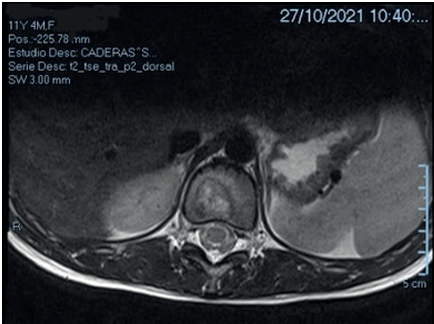

Planteos al inicio: proceso en columna toraco-lumbar de probable etiología autoinmune, infecciosa o tumoral. Se solicita paraclínica humoral para enfermedad autoinmune osteoarticular e imagen de tomografía computada (TC) y RNM. En la TC: área patológica que compromete espacio discal T11-T12, irregularidad cortical en plataforma inferior a T11, configurando zona lítica subyacente. En la RNM: foco de edema óseo en el cuerpo de T11 mayor en el platillo inferior y sobre el espacio discal T11-T12 con realce intenso asociado sin clara lesión focal delimitada, sin colapso vertebral significativo, ni masa asociada (Figuras 1 y 2).

Figura 1 Imagen de RNM de columna toracolumbar, plano sagital, obsérvese foco de edema óseo en cuerpo vertebral de T11 (asterisco).